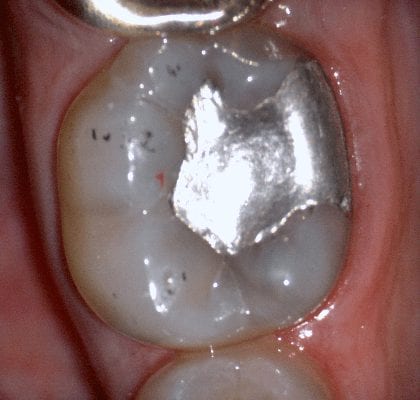

In this video we demonstrate some of the most common problems associated with second molar impressions. Usually the distal margins can be blurred by the presence of hemorrhaging or soft tissue. In this particular case, we use the tip of the camera to displace the tissue and digitall correct an area for better accuracy. The isolite systemisolite systemisolite system does a great job controlling the tongue and the lips and with proper retraction you can image a quadrant in very little time